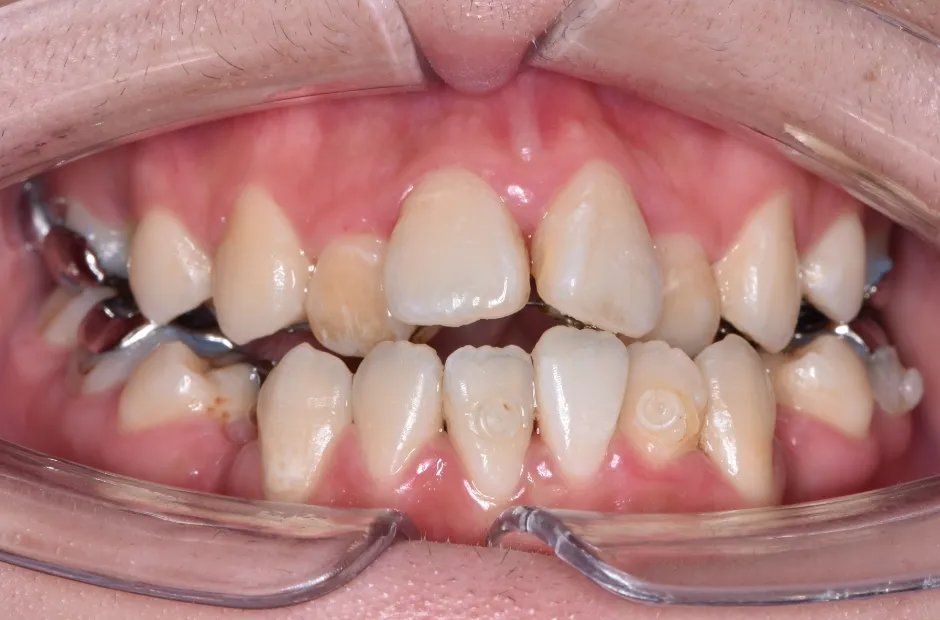

叢生

| 診断名・主訴 | 叢生 |

|---|---|

| 年齢・性別 | 43歳・女性 |

| 治療期間・回数 | 2年7か月 27回 |

| 治療に用いた主な装置 | 舌側矯正 |

| 抜歯部位 | 両顎4,4 |

| 治療費 | 100万円(税抜) |

| リスク・副作用 | 装置による違和感・疼痛・歯肉退縮・歯根吸収・虫歯のリスクなど |

治療中